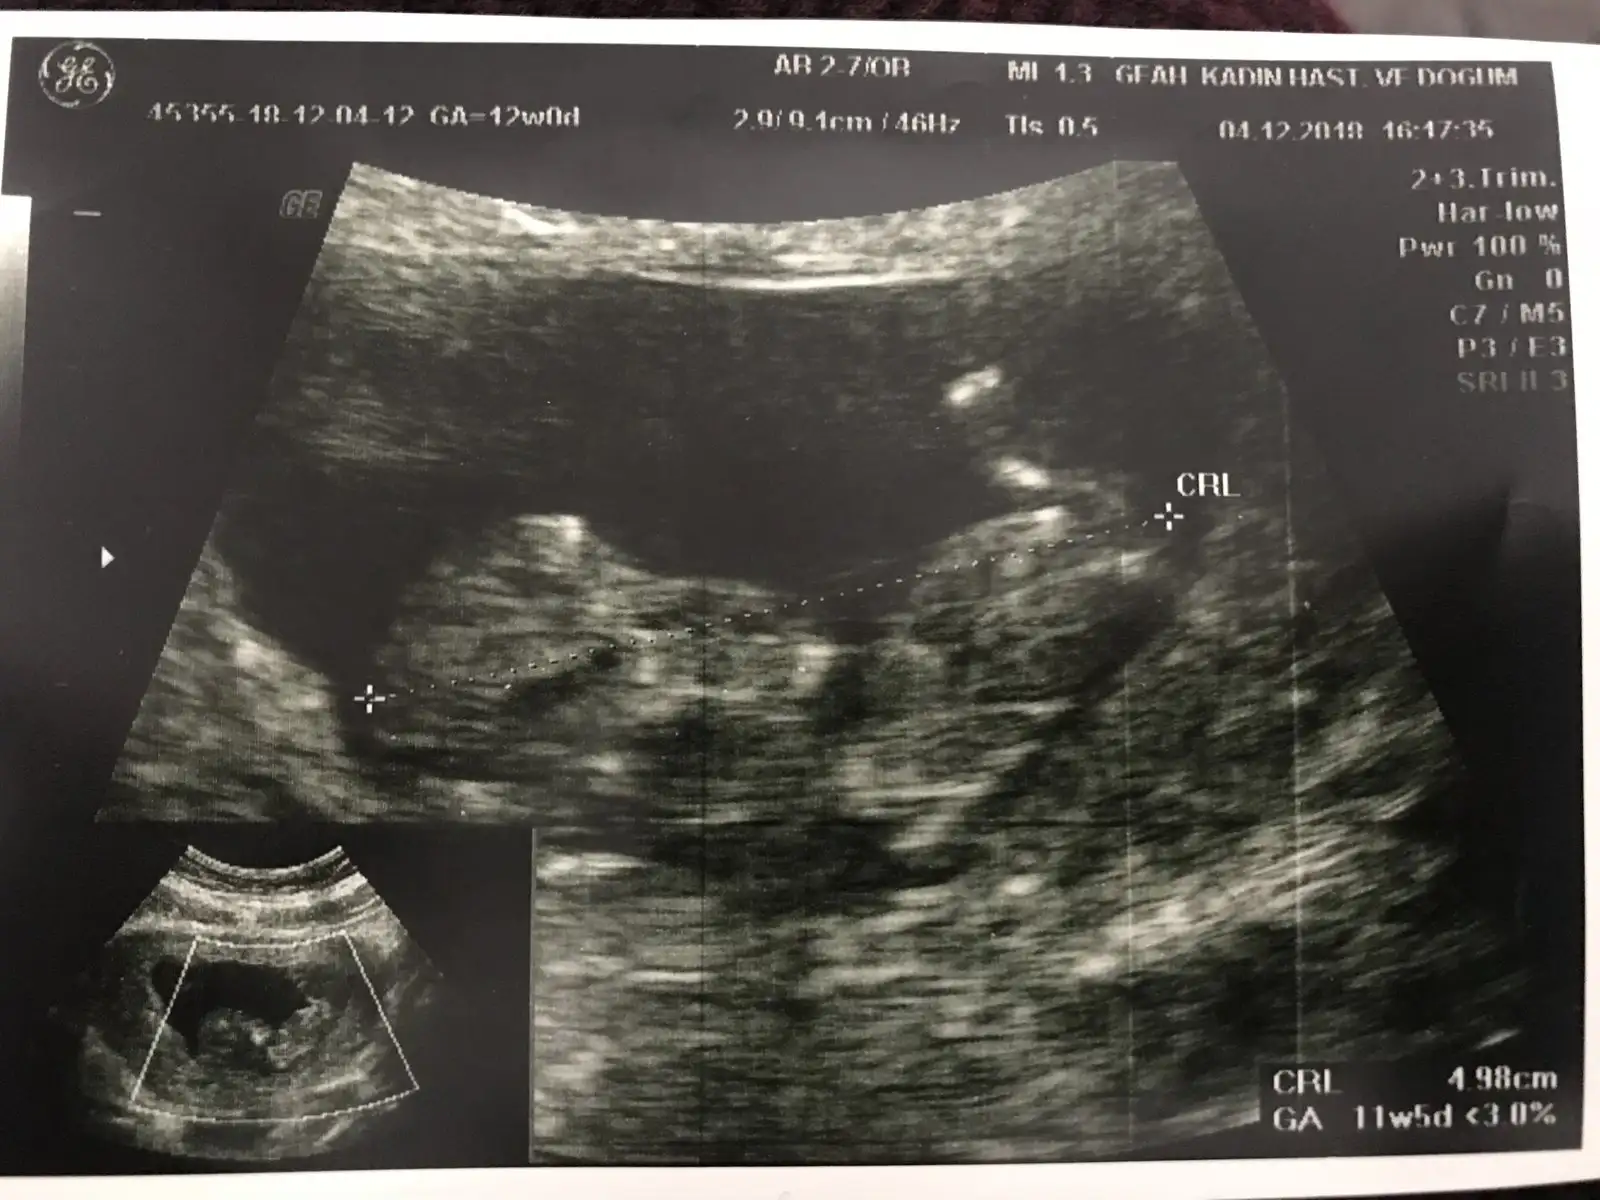

Ya canım sen bilirsin ama sorma bence çünkü cidden erken bana 11+4 te kızı andırıyor denildi 12+5 te erkek cıkıntısı var denildi yani sorduğuma pişman oldum :) 14+5te gitcem sorsam mı bilemedimyarın devlete gidicem 11+2 çıktı bugün ikili test sırasında sorsam cinsiyet tahmini yapar mı acaba. veya uzun mu sürüyor muayenesi ben az biraz anlıyorum ultrasondan ayrıntılı incelerse ssormama bile gerek kalmaz diye düşünüyorum

Ben dün gittim ikili yapacakti ama küçük su an dedi , haftaya Çarşamba gideceğim tekrar . Detaylı organ incelemesi yapacaklar . Umarım sana da erken demezler.yarın devlete gidicem 11+2 çıktı bugün ikili test sırasında sorsam cinsiyet tahmini yapar mı acaba. veya uzun mu sürüyor muayenesi ben az biraz anlıyorum ultrasondan ayrıntılı incelerse ssormama bile gerek kalmaz diye düşünüyorum